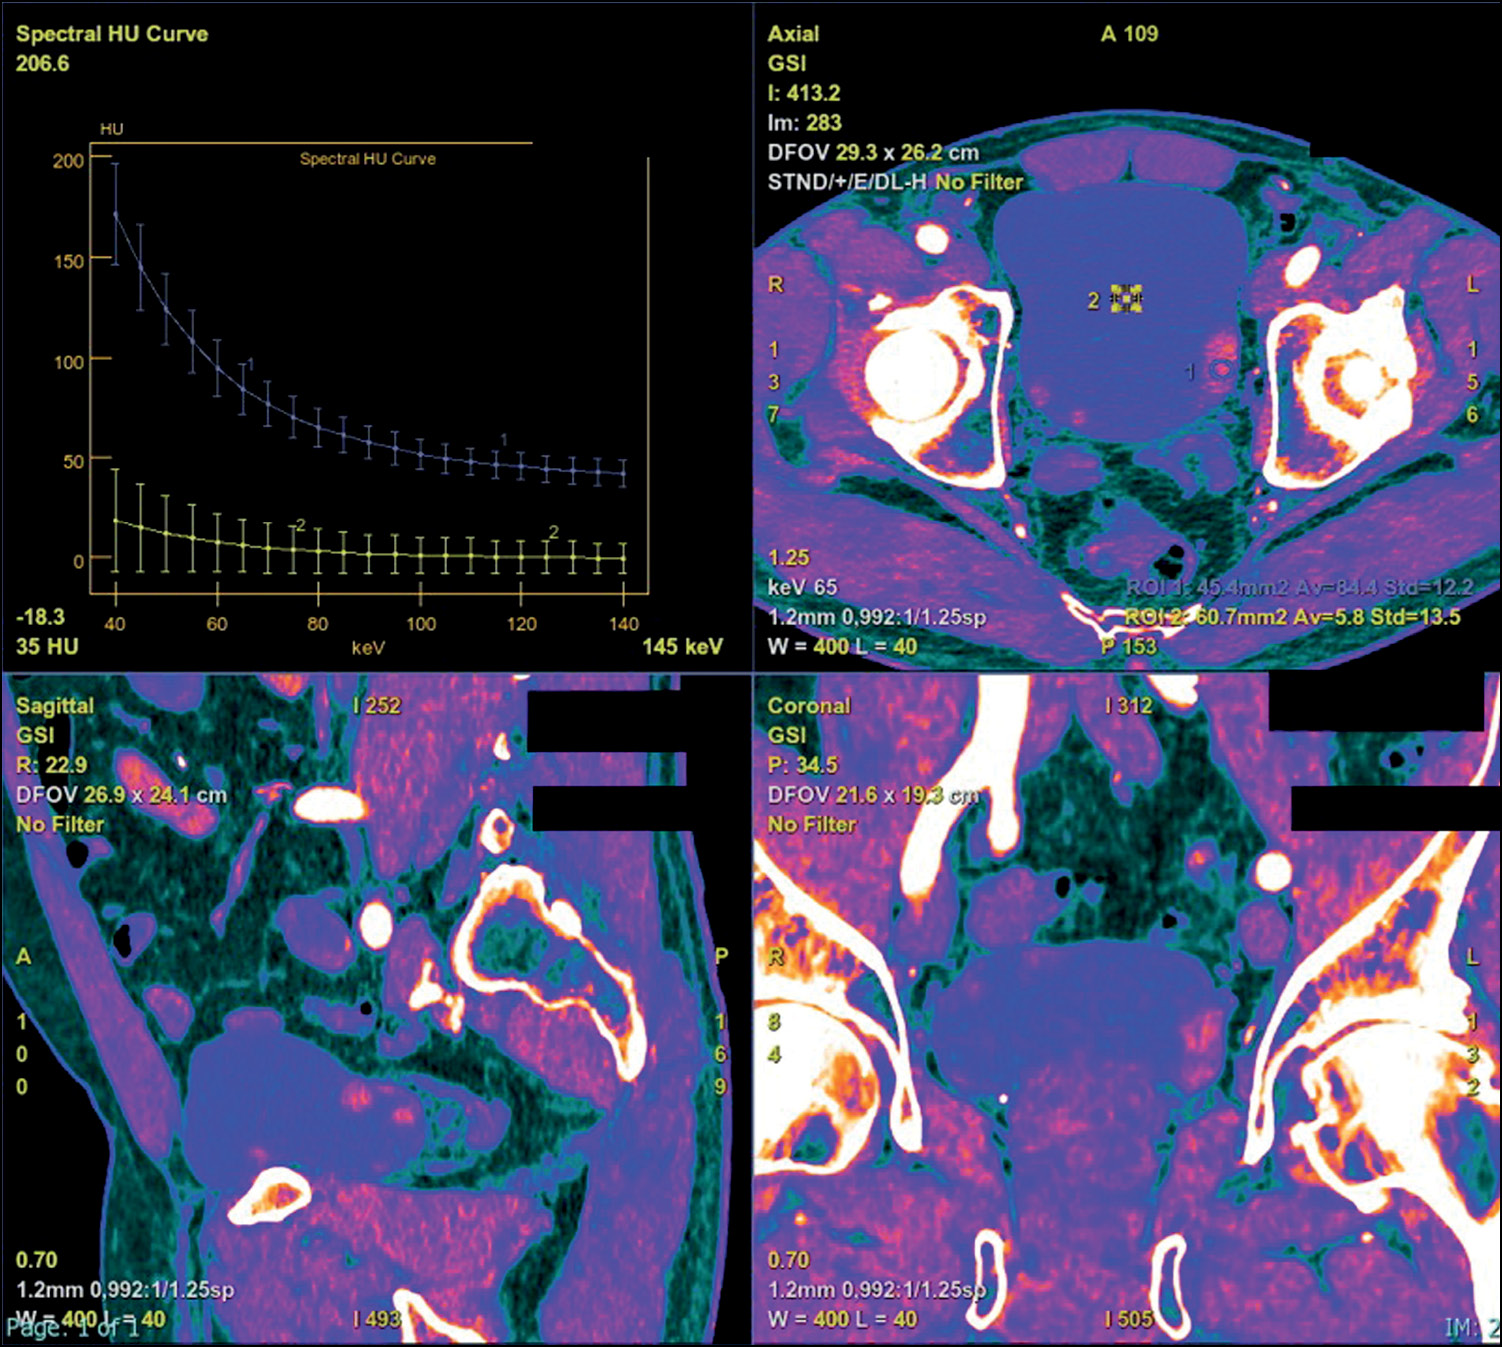

Considering the purpose of the examination such as the detection of a suspicious BCa or its staging, the most useful types of images are the virtual monochromatic (VMC), virtual non-contrast (VNC), iodine map, and atomic map.

VMC generates images similar to those of conventional single-energy CT considering quality; however, it provides more reliable attenuation values. The lower-energy kilovoltage setting can increase contrast among near structures, thanks to the high beam attenuation of iodine. Consequently, a parietal lesion is easier to recognize. The higher-energy kilovoltage setting can decrease noise and artifacts. The comparison between the two different kilovoltages settings, from VMC-acquired images, also produces a spectral attenuation curve, which is a function of energies. The latter is attributed to its properties, which are useful to improve lesion characterization.

The iodine map is a material-specific image in opposition to the iodine-removed image, as iodine is selected and not suppressed to show all areas with iodine uptake. This image results in a color map that can quantify the iodine uptake expressing it in mg/mL. Moreover, it allows for distinguishing a vascularized lesion from a nonvascularized lesion considering the amount of iodine filling the aorta.

The spectral curve, in the case of bladder wall thickening, shows a curve tending to increase from lower values of kilovoltage setting.

VMC images at low-energy kilovoltage settings generate better contrast of the tumor despite the nearby regions and increase the sensitivity in tumor detection. Moreover, by normalizing the iodine quantification to that of the aorta, in the nephrographic phase, this image type had increased specificity when a threshold of ≥3.0 mg/mL is reached and allows the differentiation of a vascular from a nonvascular lesion. The formula is as follows: |I| normalized=|I| lesion⁄|I| aorta [20, 21].

DECT advantages also concern BCa staging because iodine maps enable easier evaluation of the tumor infiltration of wall layers, including the muscular layer in differentiating an NMIBC from an MIBC and evaluating lymph node involvement and presence of metastases.

For treatment planning, the application of this technology may be crucial because it can better assess the relationship between the tumor and a vascular structure, with increased contrast obtained with the VMC at a lower kilovoltage setting, offering an important parameter (Fig. 3 and 4) [22].

Fig. 3. Multiplanar iodine map images showing different attenuations of multifocal masses, the main localized on the left posterior wall, with different Av values compared with the Av endoluminal value. The spectral curve (upper left side) allowed the characterization of materials because each material has a different attenuation curve.

Fig. 4. Multiplanar iodine map with coloring overlap showing different attenuations of multifocal masses, the main localized on the left posterior wall, with different Av values compared with the endoluminal Av value. The spectral curve (upper left side) allowed the characterization of materials because each material has a different attenuation curve.